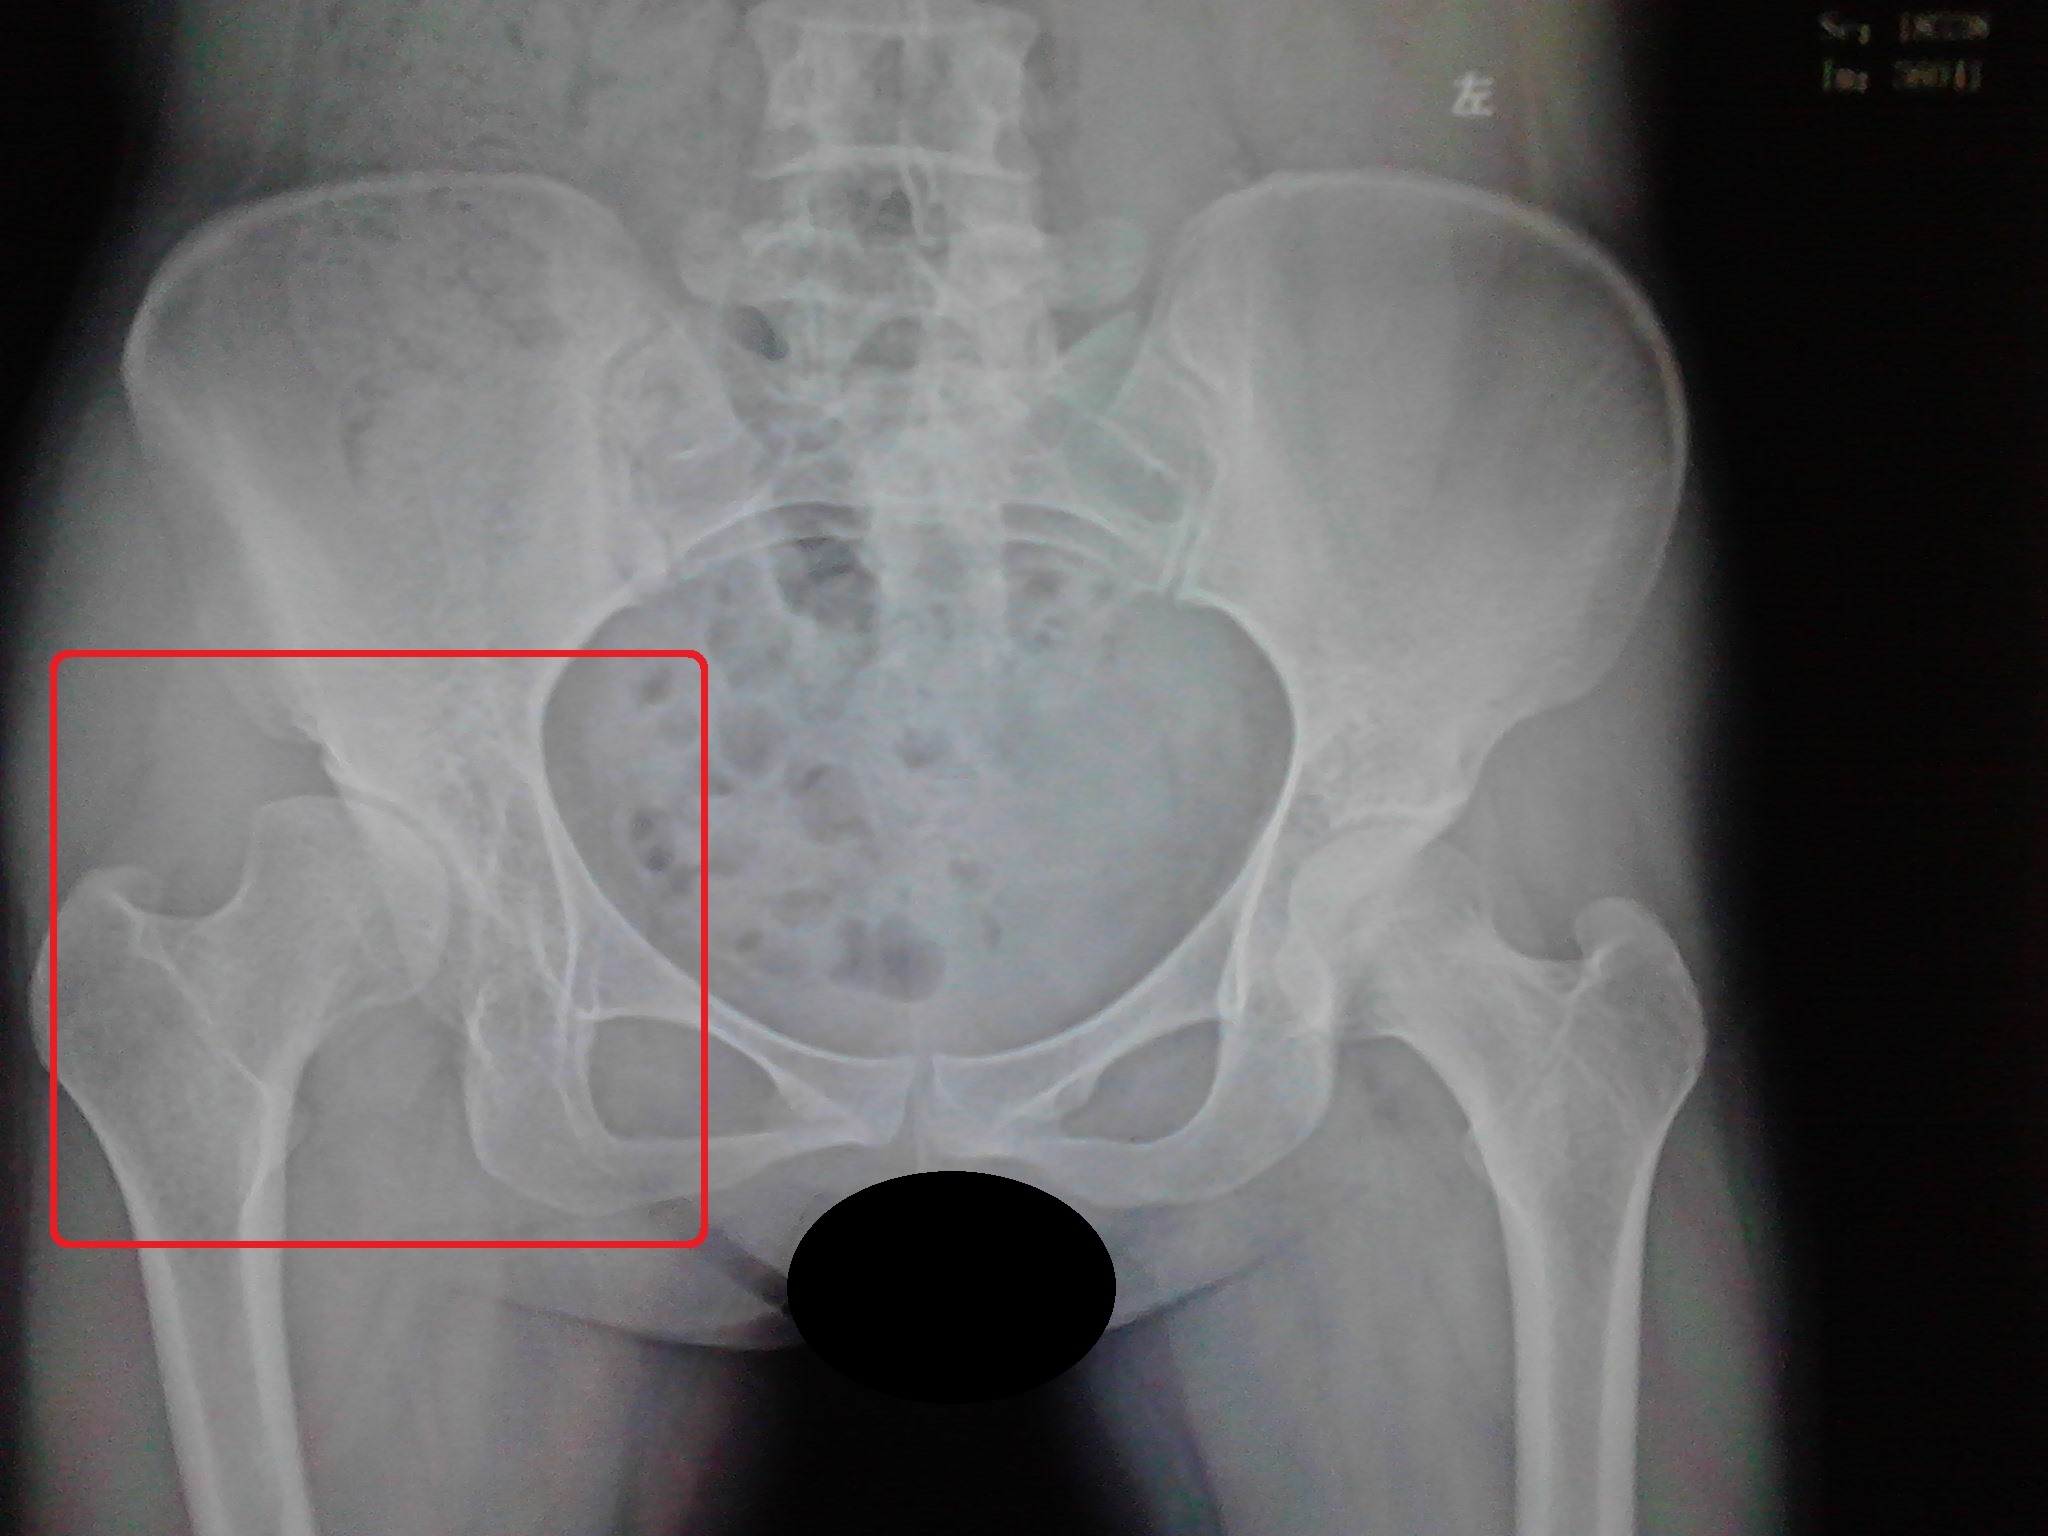

如果骨盆正位片X线上股骨头直接变塌了,不圆了,如下图所示的话,那就没其他办法了,直接做髋关节置换手术吧!(来张夸张一点的图,谁都看得清楚啦!)